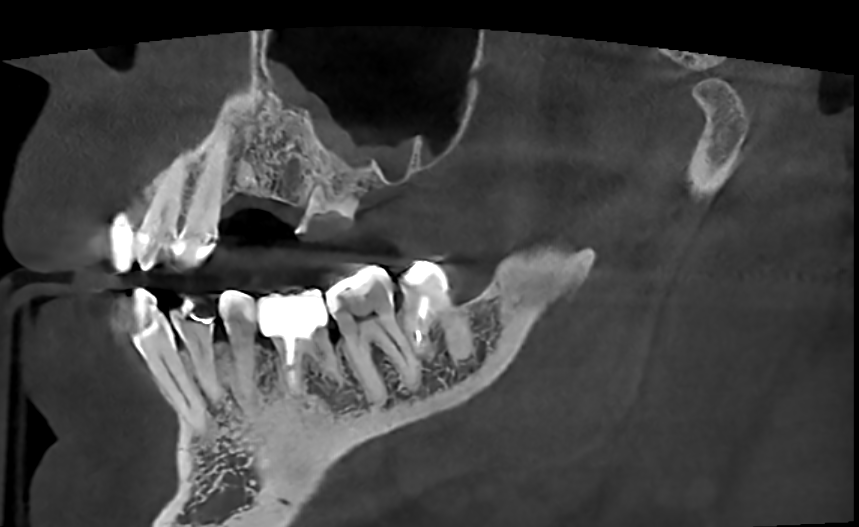

It'sGeorgy Опубликовано 28 мая, 2021 Поделиться Опубликовано 28 мая, 2021 Здравствуйте. 21.05.21: Язычносмещенный разрез, удаление оставленного корня 2.4, удаление 2.6 и 3.8. Имплантаты 2.4, 2.5. Пошел сделал снимок: Не понравился дистальный наклон 2.5, пошел перекручивать. Пока крутил-вертел торк с 25 упал до пальцевого. Принял решение установки коротких формиков, ССТ вестибулярно и ушивания наглухо. Сегодня пациент пришел на осмотр к другому доктору, а там вот такая печалька: Какие ошибки предполагаю сам: 1. Слишком толстый трансп, ушивание которого вызвало перенатяжение 2. Медиальный шов, который держит трансп совсем хиленький и, на самом деле, мало что держит. И главный вопрос: что делать? Оставлять и надеяться, что что-то приживется или полностью убирать? Ссылка на комментарий

It'sGeorgy Опубликовано 29 мая, 2021 Автор Поделиться Опубликовано 29 мая, 2021 (изменено) Всем спасибо за отклик. Через 2 мес, если не забуду, выложу фото результата. 28.05.2021 в 22:17, АнтонТЛТ сказал: Какой смысл в свободном трансплантате был? По плану было увеличить объем вестибулярно и толщину окклюзионно, чтобы в дальнейшем, на этапе времяшек, дополнительно сместить все в сторону этого дефекта, чтобы его закрыть: 11 часов назад, Женька сказал: Не слишком ли высоко трансплантат забран? не критикую, только интересуюсь. Сложно сказать. При заборе трансп с неба я иглой во время анестезии смотрю участок, где достаточная толщина. Вероятно, в момент операции, эта область показалась наиболее перспективной с этой точки зрения. Сейчас, как сказал @Карен Аванесов , я бы вообще с бугра взял. Да и в целом, с десной бы работал на этапе высоких формиков. Изменено 29 мая, 2021 пользователем It'sGeorgy Ссылка на комментарий

АнтонТЛТ Опубликовано 2 июня, 2021 Поделиться Опубликовано 2 июня, 2021 (изменено) Я правильно понимаю, что установлены короткие фдм, подшит трансплантат, не было мобилизации и рана ушита наглухо? Если да, то за счёт чего получилось ушить наглухо? Трансплантат получается не вестибулярно, а окклюзионно пришит. И рана ушита с чрезмерным натяжением. Есть фото со швами? Трансплантат фиксирован обычным П-образным швом? Изменено 2 июня, 2021 пользователем АнтонТЛТ Ссылка на комментарий

It'sGeorgy Опубликовано 12 июня, 2021 Автор Поделиться Опубликовано 12 июня, 2021 Прошу прощения, что долго не получилось ответить. 03.06.2021 в 00:11, АнтонТЛТ сказал: Я правильно понимаю, что установлены короткие фдм, подшит трансплантат, не было мобилизации и рана ушита наглухо? Верно. 03.06.2021 в 00:11, АнтонТЛТ сказал: Если да, то за счёт чего получилось ушить наглухо? Выходит, что за счет излишнего натяжения. Но, во время операции, мне не показалось, что я сильно что-то тягу. 03.06.2021 в 00:11, АнтонТЛТ сказал: Трансплантат получается не вестибулярно, а окклюзионно пришит. Да. В целом, хотел, чтобы было так: Трансп лежит частично над имплантатами, частично - вестибулярно под лоскутом. Лоскут фиксируется небно . 03.06.2021 в 00:11, АнтонТЛТ сказал: Трансплантат фиксирован обычным П-образным швом? Да, двумя. 03.06.2021 в 00:11, АнтонТЛТ сказал: Есть фото со швами? К сожалению, нет. Вот так вот это выглядело вчера. По-моему, десна возвращается в состояние, которое было до операции. Дальше по плану долгожданная чистка + коррекция домашней гигиены и лечение всего того, что надо полечить. Через 1.5 мес буду открывать имплантаты и устанавливать высокие формики и думать, что дальше. Ссылка на комментарий

АнтонТЛТ Опубликовано 12 июня, 2021 Поделиться Опубликовано 12 июня, 2021 (изменено) Какие ошибки вижу. 1)Разрез смещен небно, сосуды кровоснабжающие десну идут вестибулярно и небно, на вершине альвеолярного отростка самые конечные "ветви", т.е. самые тонкие. Из-за небного разреза край вестибулярного лоскута потерял часть питания. 2) Лоскут ушит с натяжением, т.к. не было мобилизации, и где были швы лоскут пережат. Опять же нарушение питания. 3) Трансплантат пришит большими П-образным швами, которые пережимают сосуды вестибулярного лоскута. 4) Трансплантат лежит поверх имплантатов, значит ушивание раны было не стык в стык. И рассчитывать на заживление первичным натяжением не особо нужно. 5) Про толщину трансплантата уже было сказано, могу добавить что трансплантат должен питаться от покрывающего лоскута и от кости. Площадь контакта с костью снижена из-за наличия имплантатов. Изменено 12 июня, 2021 пользователем АнтонТЛТ 3 Ссылка на комментарий

Irouil Опубликовано 12 июня, 2021 Поделиться Опубликовано 12 июня, 2021 Практически слово в слово согласен с Антоном Потребители кровоснабжения - трансплант и края раны. Доноры - кость и основания лоскутов. В Вашем случае графт отнимает у вестибулярного края раны и от основания, и от кости. Сам он, при этом, недополучает от кости из-за железок, на которых лежит, следовательно просит у лоскута еще больше. Зато небный край раны получает избыток питания, который там нафиг не нужен. 1 Ссылка на комментарий